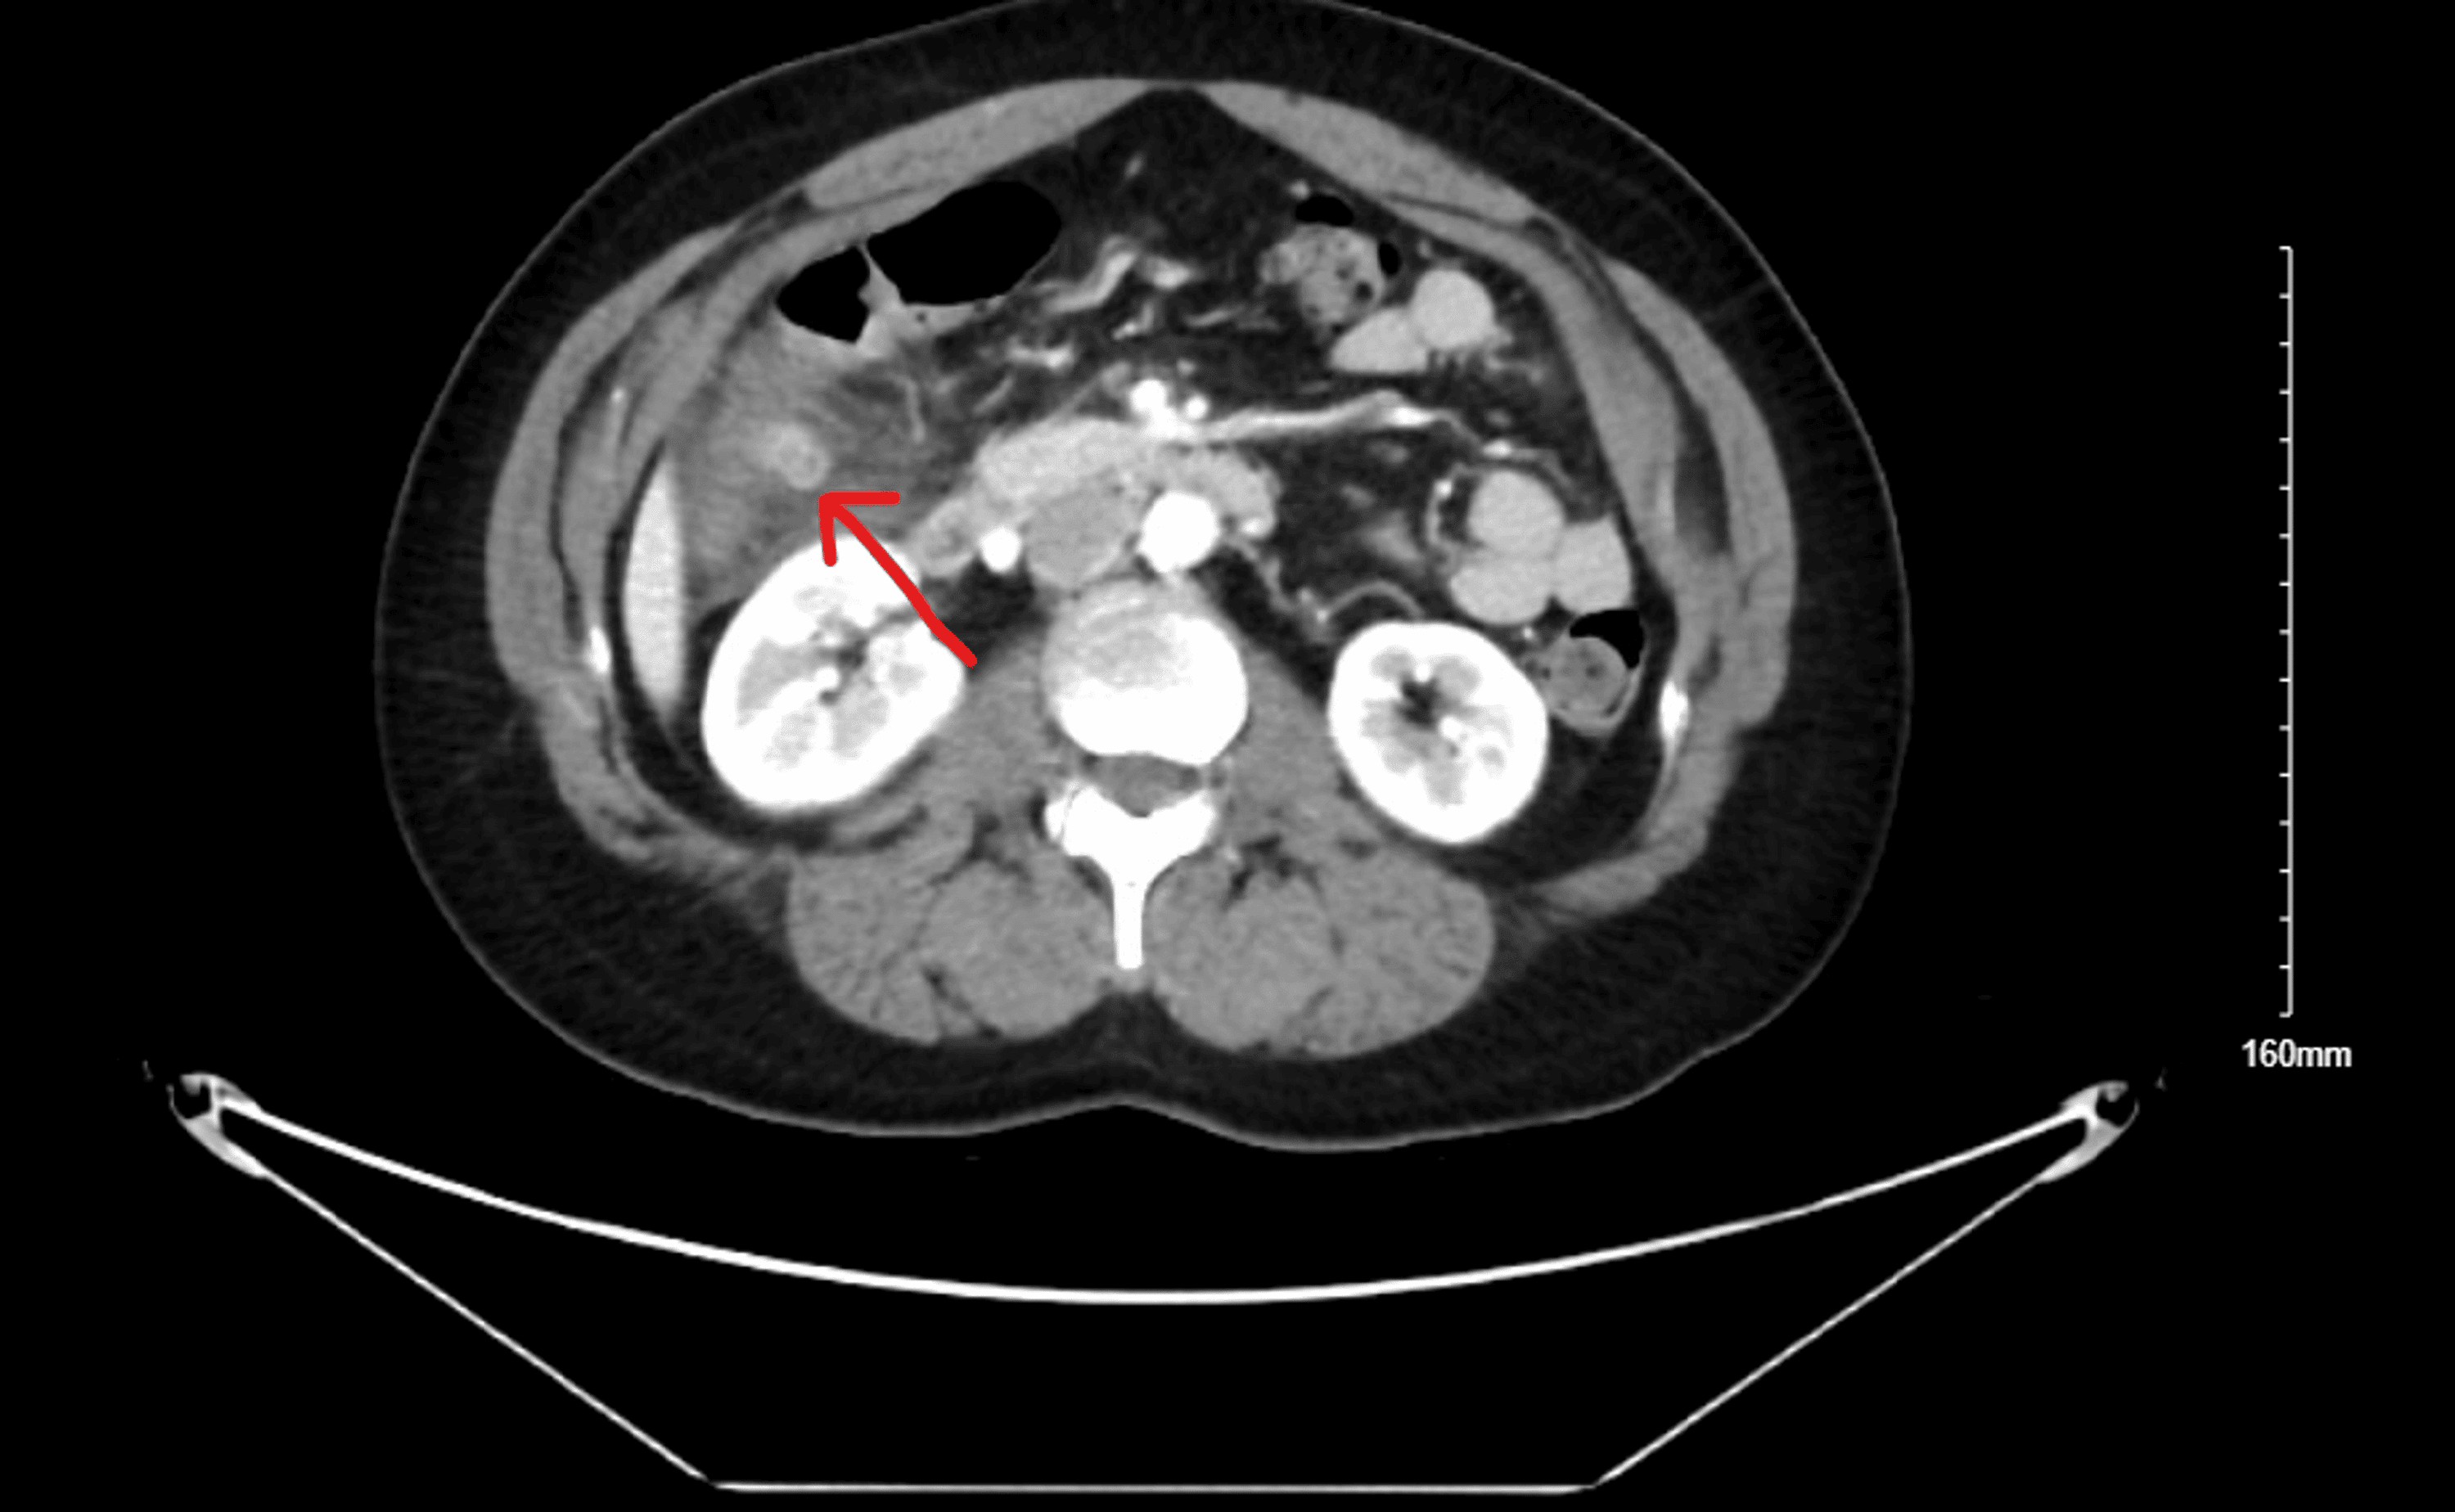

A NCCT abdomen showing mild thickening of wall of hepatic flexure

A NCCT abdomen showing mild thickening of wall of hepatic flexure Hepatic Flexure Inflammation A large bowel stricture with shouldering at the hepatic flexure consistent with colonic carcinoma. The axial abdominal computed tomogram shows a shouldered colonic stricture at. 1 what does the scan show and what is the most likely underlying diagnosis? The hepatic immune system is designed to tolerate diverse harmless foreign moieties to maintain homeostasis in the. Colorectal emergencies are a. Hepatic Flexure Inflammation.

A NCCT abdomen showing mild thickening of wall of hepatic flexure Hepatic Flexure Inflammation A large bowel stricture with shouldering at the hepatic flexure consistent with colonic carcinoma. Either collagen or lymphocytes (a type of white blood cell) infiltrate into the layers of the wall of the colon,. Imaging the hepatic flexure can identify conditions such as colonic tumors and inflammatory bowel diseases. The axial abdominal computed tomogram shows a shouldered colonic stricture at.. Hepatic Flexure Inflammation.